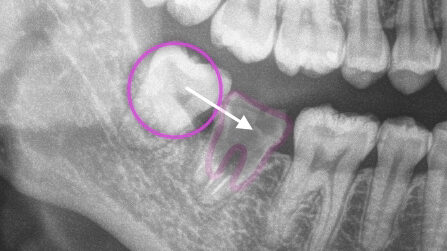

移植に適した歯の形態

移植歯として使う歯の「歯の根の形が複雑ではないこと」が重要です。

一般的に歯の根は、歯の種類や・人によって本数や形態が異なります。

まっすぐな根もあれば、大きく曲がっている場合もあります。

歯の移植をする場合には、歯の根が少なかったり、根どうしが癒着して比較的シンプルな形をしているほうが歯根膜を傷つけずに済み、成功率が上がります。

そのため、歯の根のかたちが複雑すぎる場合は、そもそも移植歯として適していないといえます。